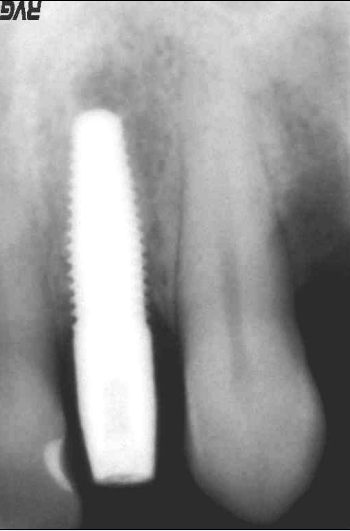

Lo scopo del presente lavoro quello di dimostrare i reali vantaggi che una tecnica delicata, come quella post-estrattiva offre nel riabilitare protesicamente un settore ad alta rilevanza estetica. Il paziente in esame presentava una frattura coronale del 22 devitalizzato, con lesione granulomatosa peri-apicale. Su richiesta del paziente veniva applicata una corona provvisoria e programmato per un impianto post-estrattivo. Le condizioni cliniche del paziente erano buone per cui si procedeva alla pianificazione del caso. Pianificazione che prevedeva, lestrazione del 22 con asportazione del granuloma peri-apicale, disinfezione, cruentazione dellalveolo, ed applicazione di un impianto Nobel-Direct (3.5 x 13 mm). La valutazione intra-operatoria dellaltezza alveolare, della distanza crestale vestibolo-palatale e mesio-distale, facevano propendere per linserimento di un impianto Nobel-Direct della dimensione 4.3 x 13 mm senza fresatura alveolare, ma semplicemente avvitandolo nellalveolo e raggiungendo una forza di serraggio > di 45 N. Preparare il sito implantare per una maggiore profondit avrebbe creato problemi per lasse implantare determinando una eccessiva vestibolarizzazione del moncone. Si procedeva allapplicazione ed alladattamento del provvisorio dopo una piccola correzione del moncone. Nota importante da sottolineare il perfetto adattamento del provvisorio, non solo al pilastro implantare ma anche alla mucosa gengivale, dove soprattutto nellimplantologia post-estrattiva lemergenza dellimpianto non sar mai perfettamente aderente n alla cresta alveolare, quasi sempre a sezione ovalare, n alla mucosa gengivale. Il sigillo mucosale garantisce la formazione ed il mantenimento di quel coagulo ematico che andr a colmare il gap tra osso, impianto e corona, impedendo laccumulo di residui alimentari e di placca, che minerebbero sicuramente questa zona critica. Si comprende pertanto che il provvisorio non deve invadere uno spazio che non gli compete, ma deve occupare sicuramente quello spazio che prima competeva alla corona riproducendo perfettamente gli stessi rapporti con i tessuti limitrofi. Al paziente veniva consigliata una copertura antibiotica (Amoxicillina cpr 1 gr/12 ore x 5 gg,; Efferalgan cpr 1 cpr alloccorrenza; Dentosan collutorio 0,20% - 3-4 sciacqui al die x 10 gg) evitare sovraccarichi masticatori, di poter incidere ma di non strappare i cibi. Il paziente veniva controllato dopo 7 giorni, ad 1 mese ed al terzo mese, periodo questultimo in cui si procedeva ad un controllo rx endorale alla preparazione del pilastro con ribasatura del provvisorio. Dopo circa 7 giorni si rilevavano le impronte di precisione e quindi si finalizzava il lavoro. Possiamo ritenerci soddisfatti del risultato finale, sia clinico, che radiografico ed estetico, considerando le difficolt presentatesi durante lintervento. Tra queste annoveriamo sicuramente lestrazione del residuo radicolare, devitalizzato, con granuloma peri-apicale e lesiguit della corticale vestibolare, che doveva essere assolutamente conservata. Il risultato estetico finale, tessuti molli e corona dentaria, sicuramente soddisfacente, e deriva da una cura minuziosa dei particolari chirurgici e protesici, sempre nel rispetto massimo dei tessuti.

Il paziente in esame stato sottoposto ad estrazione del residuo radicolare del 22 con asportazione di granuloma peri-apicale ed inserimento contestuale di una fixture monofasica (Nobeldirect) con protesi fissa provvisoria. Il caso stato completato con protesi fissa oro-ceramica dopo tre mesi dall'intervento.